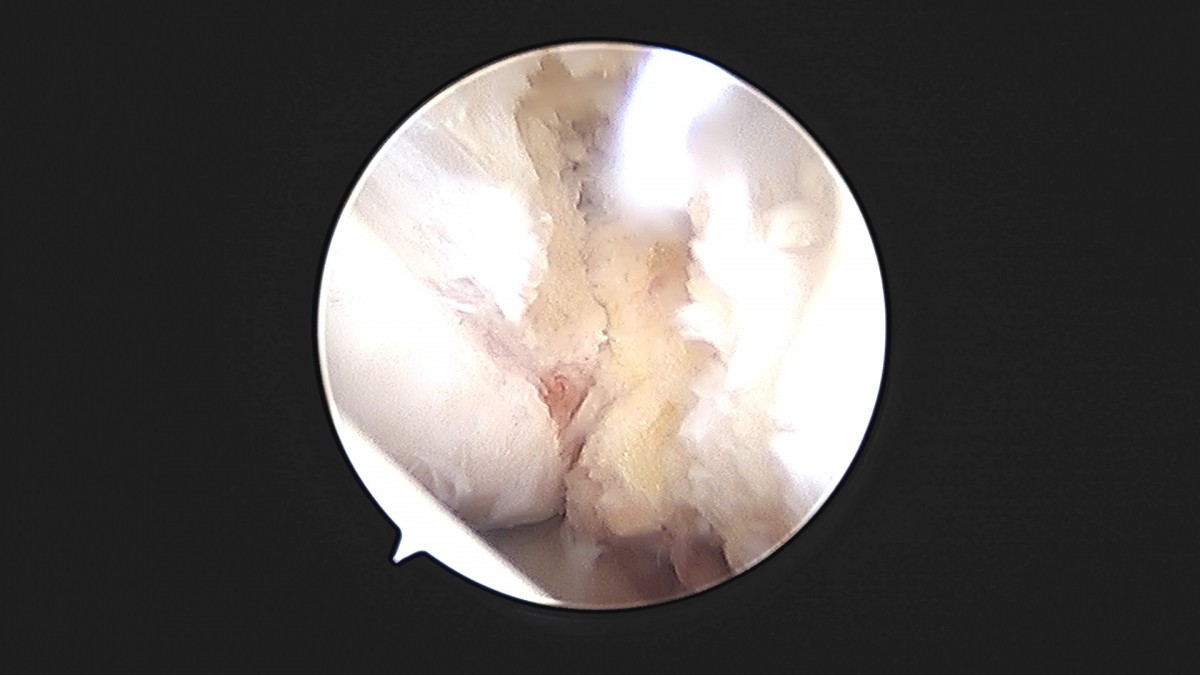

이재상원장님 발목 인대 봉합술 이주O 환자

dae765e4d9ac96aee867c9d6292d8784_1758007210_0844.jpg